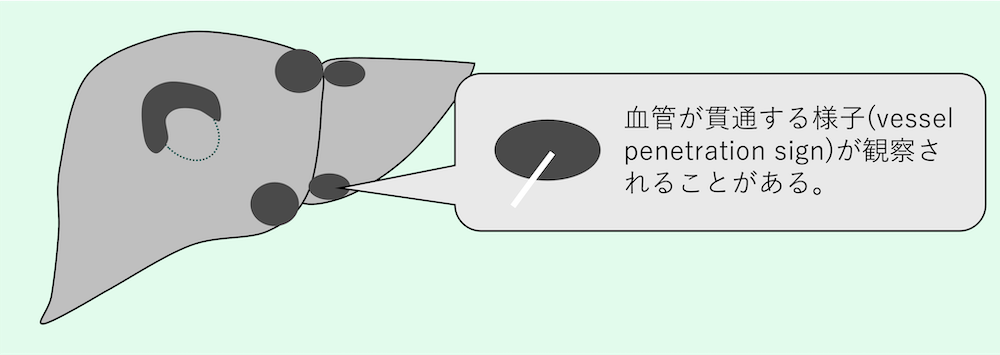

いずれの場合も、病変内を走行する血管(門脈や肝静脈)が圧排・屈曲されることなく貫通する「vessel penetration sign」が重要な良性の指標となる。

- 内部の血管貫通:病変内を血管が正常に走行しているか(vessel penetration)。